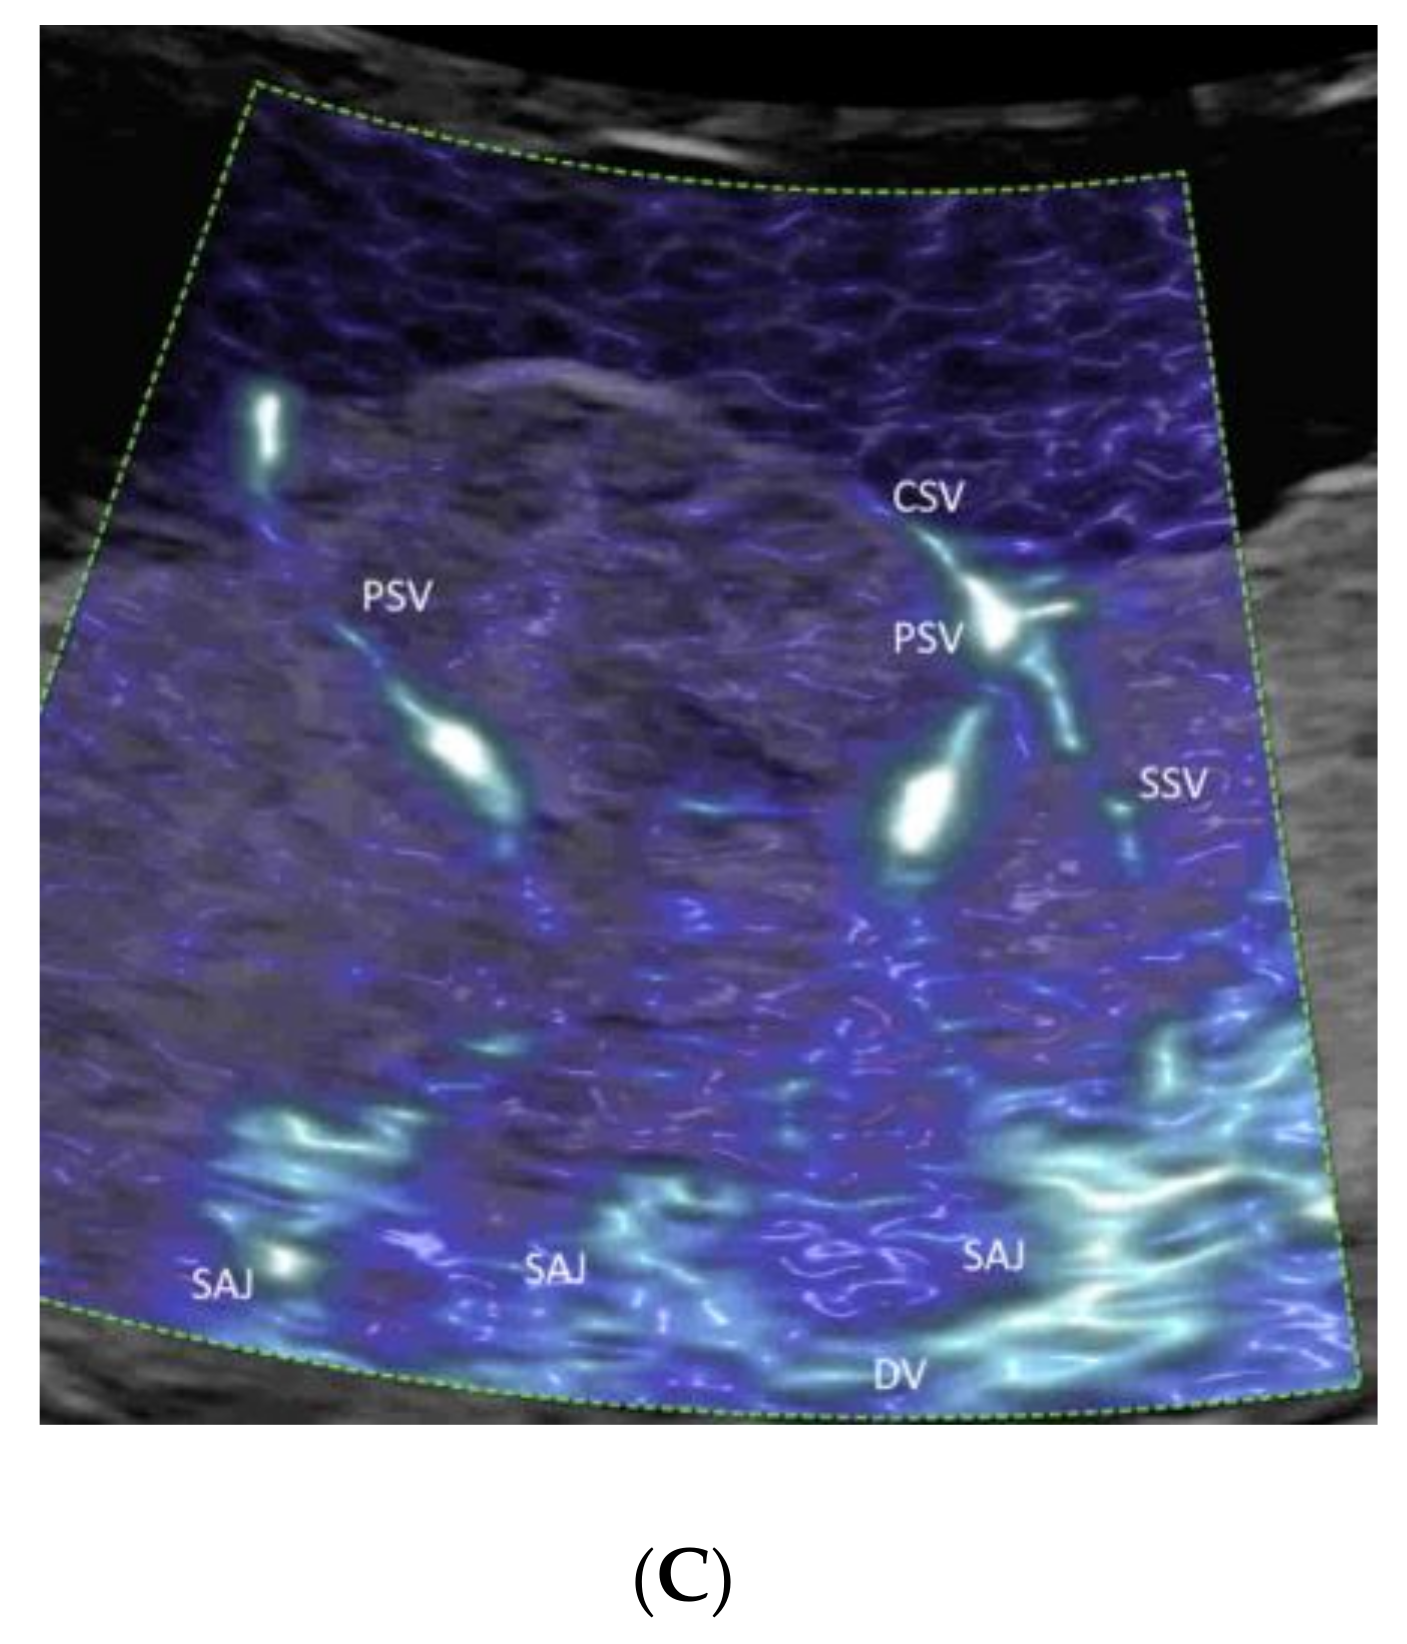

4.5. Umbilical Cord

- Leung, K.Y. Imaging of fetal precordial venous system by four-dimensional ultrasound with spatiotemporal image correlation technology. J. Clin. Ultrasound 2021. [Google Scholar] [CrossRef]